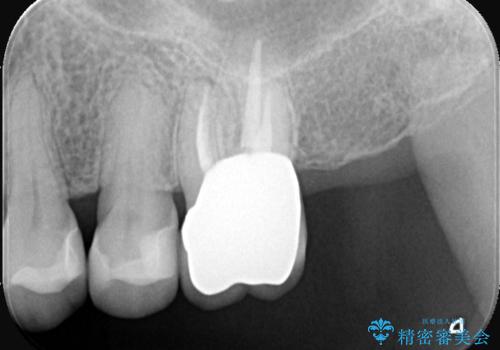

根の状態が安定した後、金属を一切使用しないオールセラミッククラウンを装着しました。高い適合精度により二次感染のリスクを抑え、天然歯に近い透明感と耐久性を両立させています。根の違和感も解消され、機能・審美ともに健康な状態を取り戻しました。